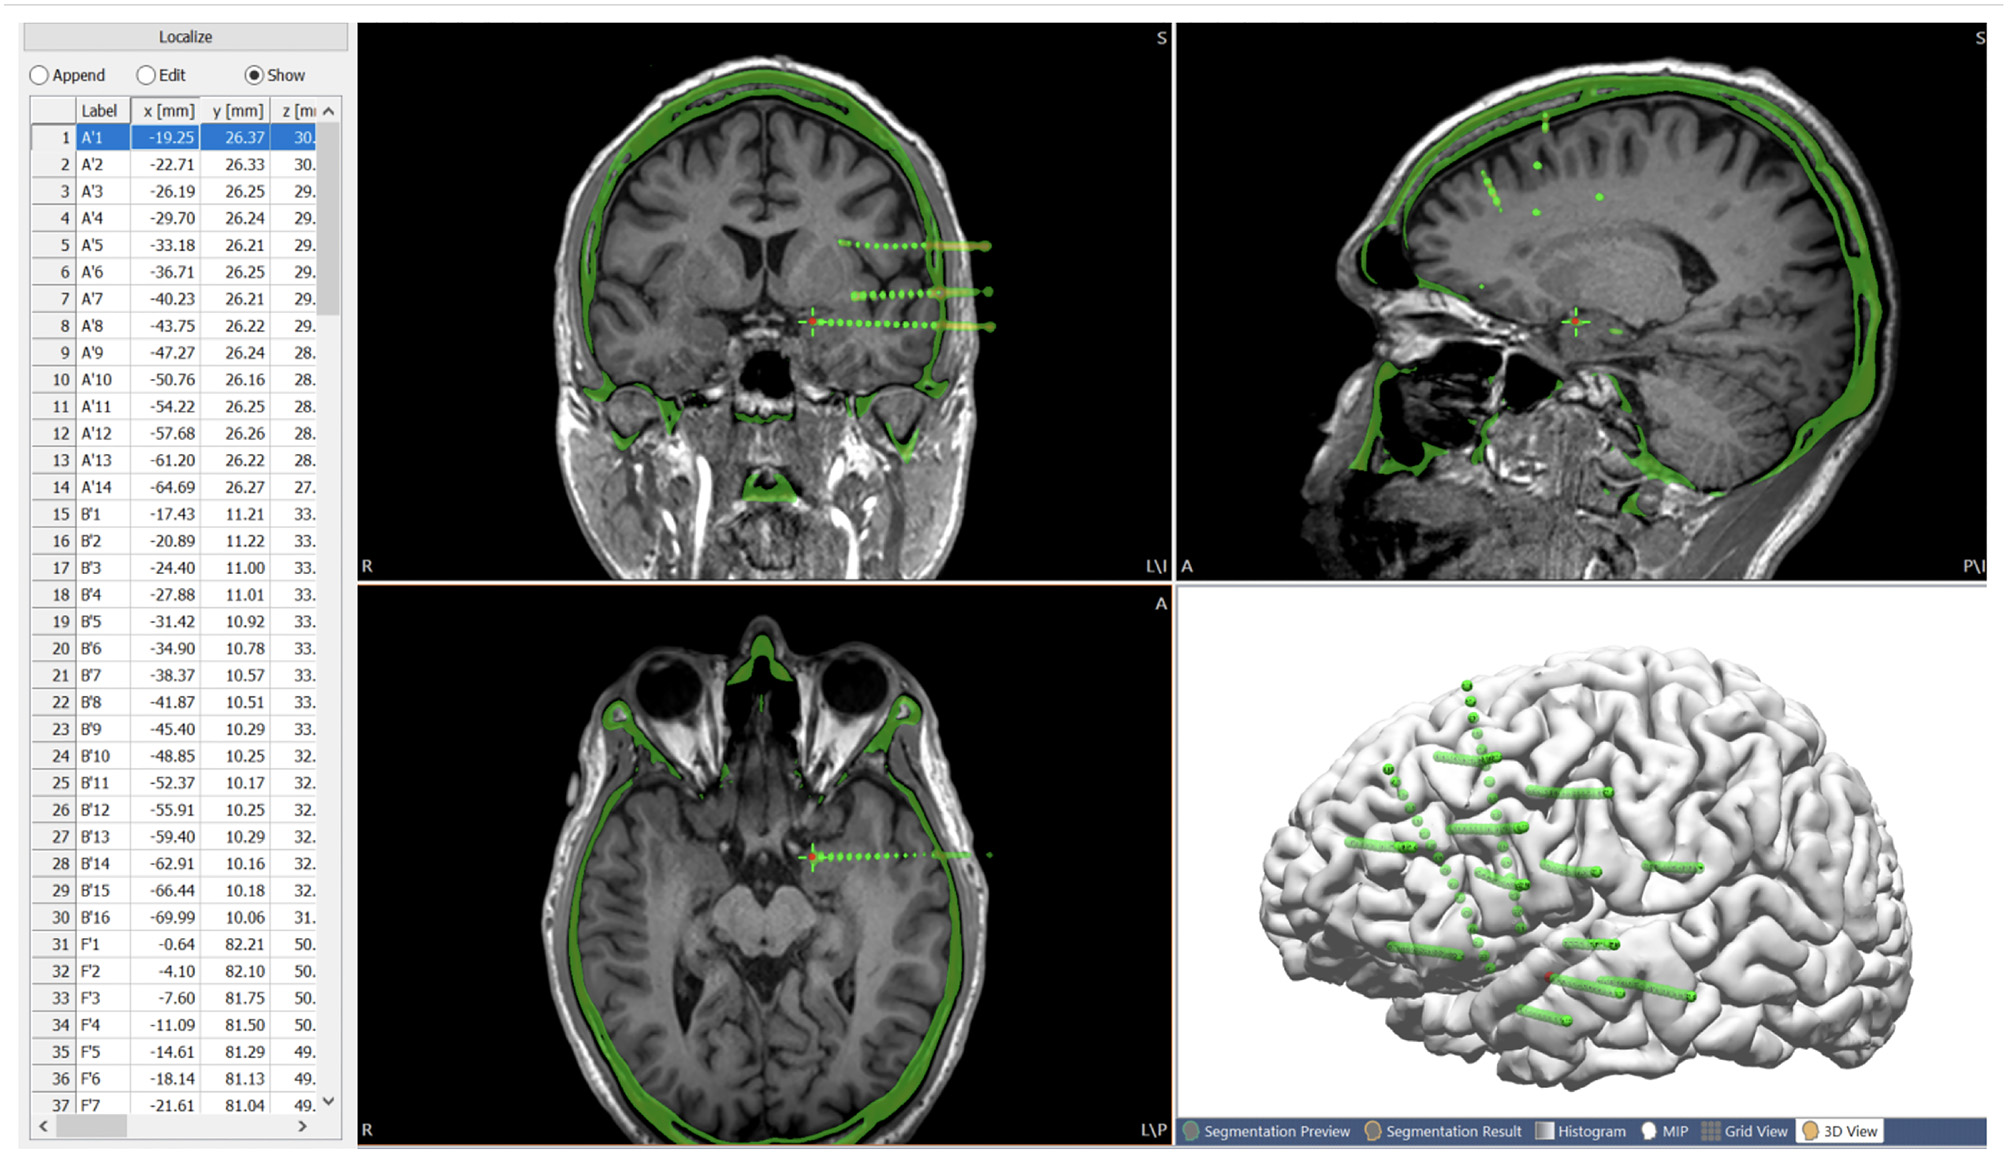

A high-resolution CT was taken immediately after the ICEEG implantation (SEEG or subdural grid and depth implantation), and the images were used to indicate the location of the implanted electrodes. After fusing with the T1-weighted base image, all electrode contacts were segmented from the CT (the center of maximal intensity was taken as the electrode contact location), and stored as a list of localize points with coordinates for the electrode contacts. The contacts were individually named and displayed in an interactive fashion. This is shown in Figure 4.

Figure 4

Post-SEEG-implantation CT images co-registered with the T1-weighted base image, with all the electrode contacts segmented from the CT (center of highest intensity) and stored as a list of localize points with coordinates for the electrode contacts. Green spheres indicate extracted electrode contacts. Red contact indicates the current electrode contact (highlighted on the list of localize points), the location of which is synchronized on the MRI and CT.

Analysis of ICEEG Data in Conjunction With Non-invasive Modalities

Since the non-invasive modalities were all registered to the same space of the T1-weighted base image volume, once the post-implantation CT image was co-registered to the base image volume, direct comparison between the ICEEG data and the non-invasive evaluation data was immediately feasible. This facilitates straightforward comparisons of the localization results from non-invasive modalities with the interictal and ictal findings from ICEEG.